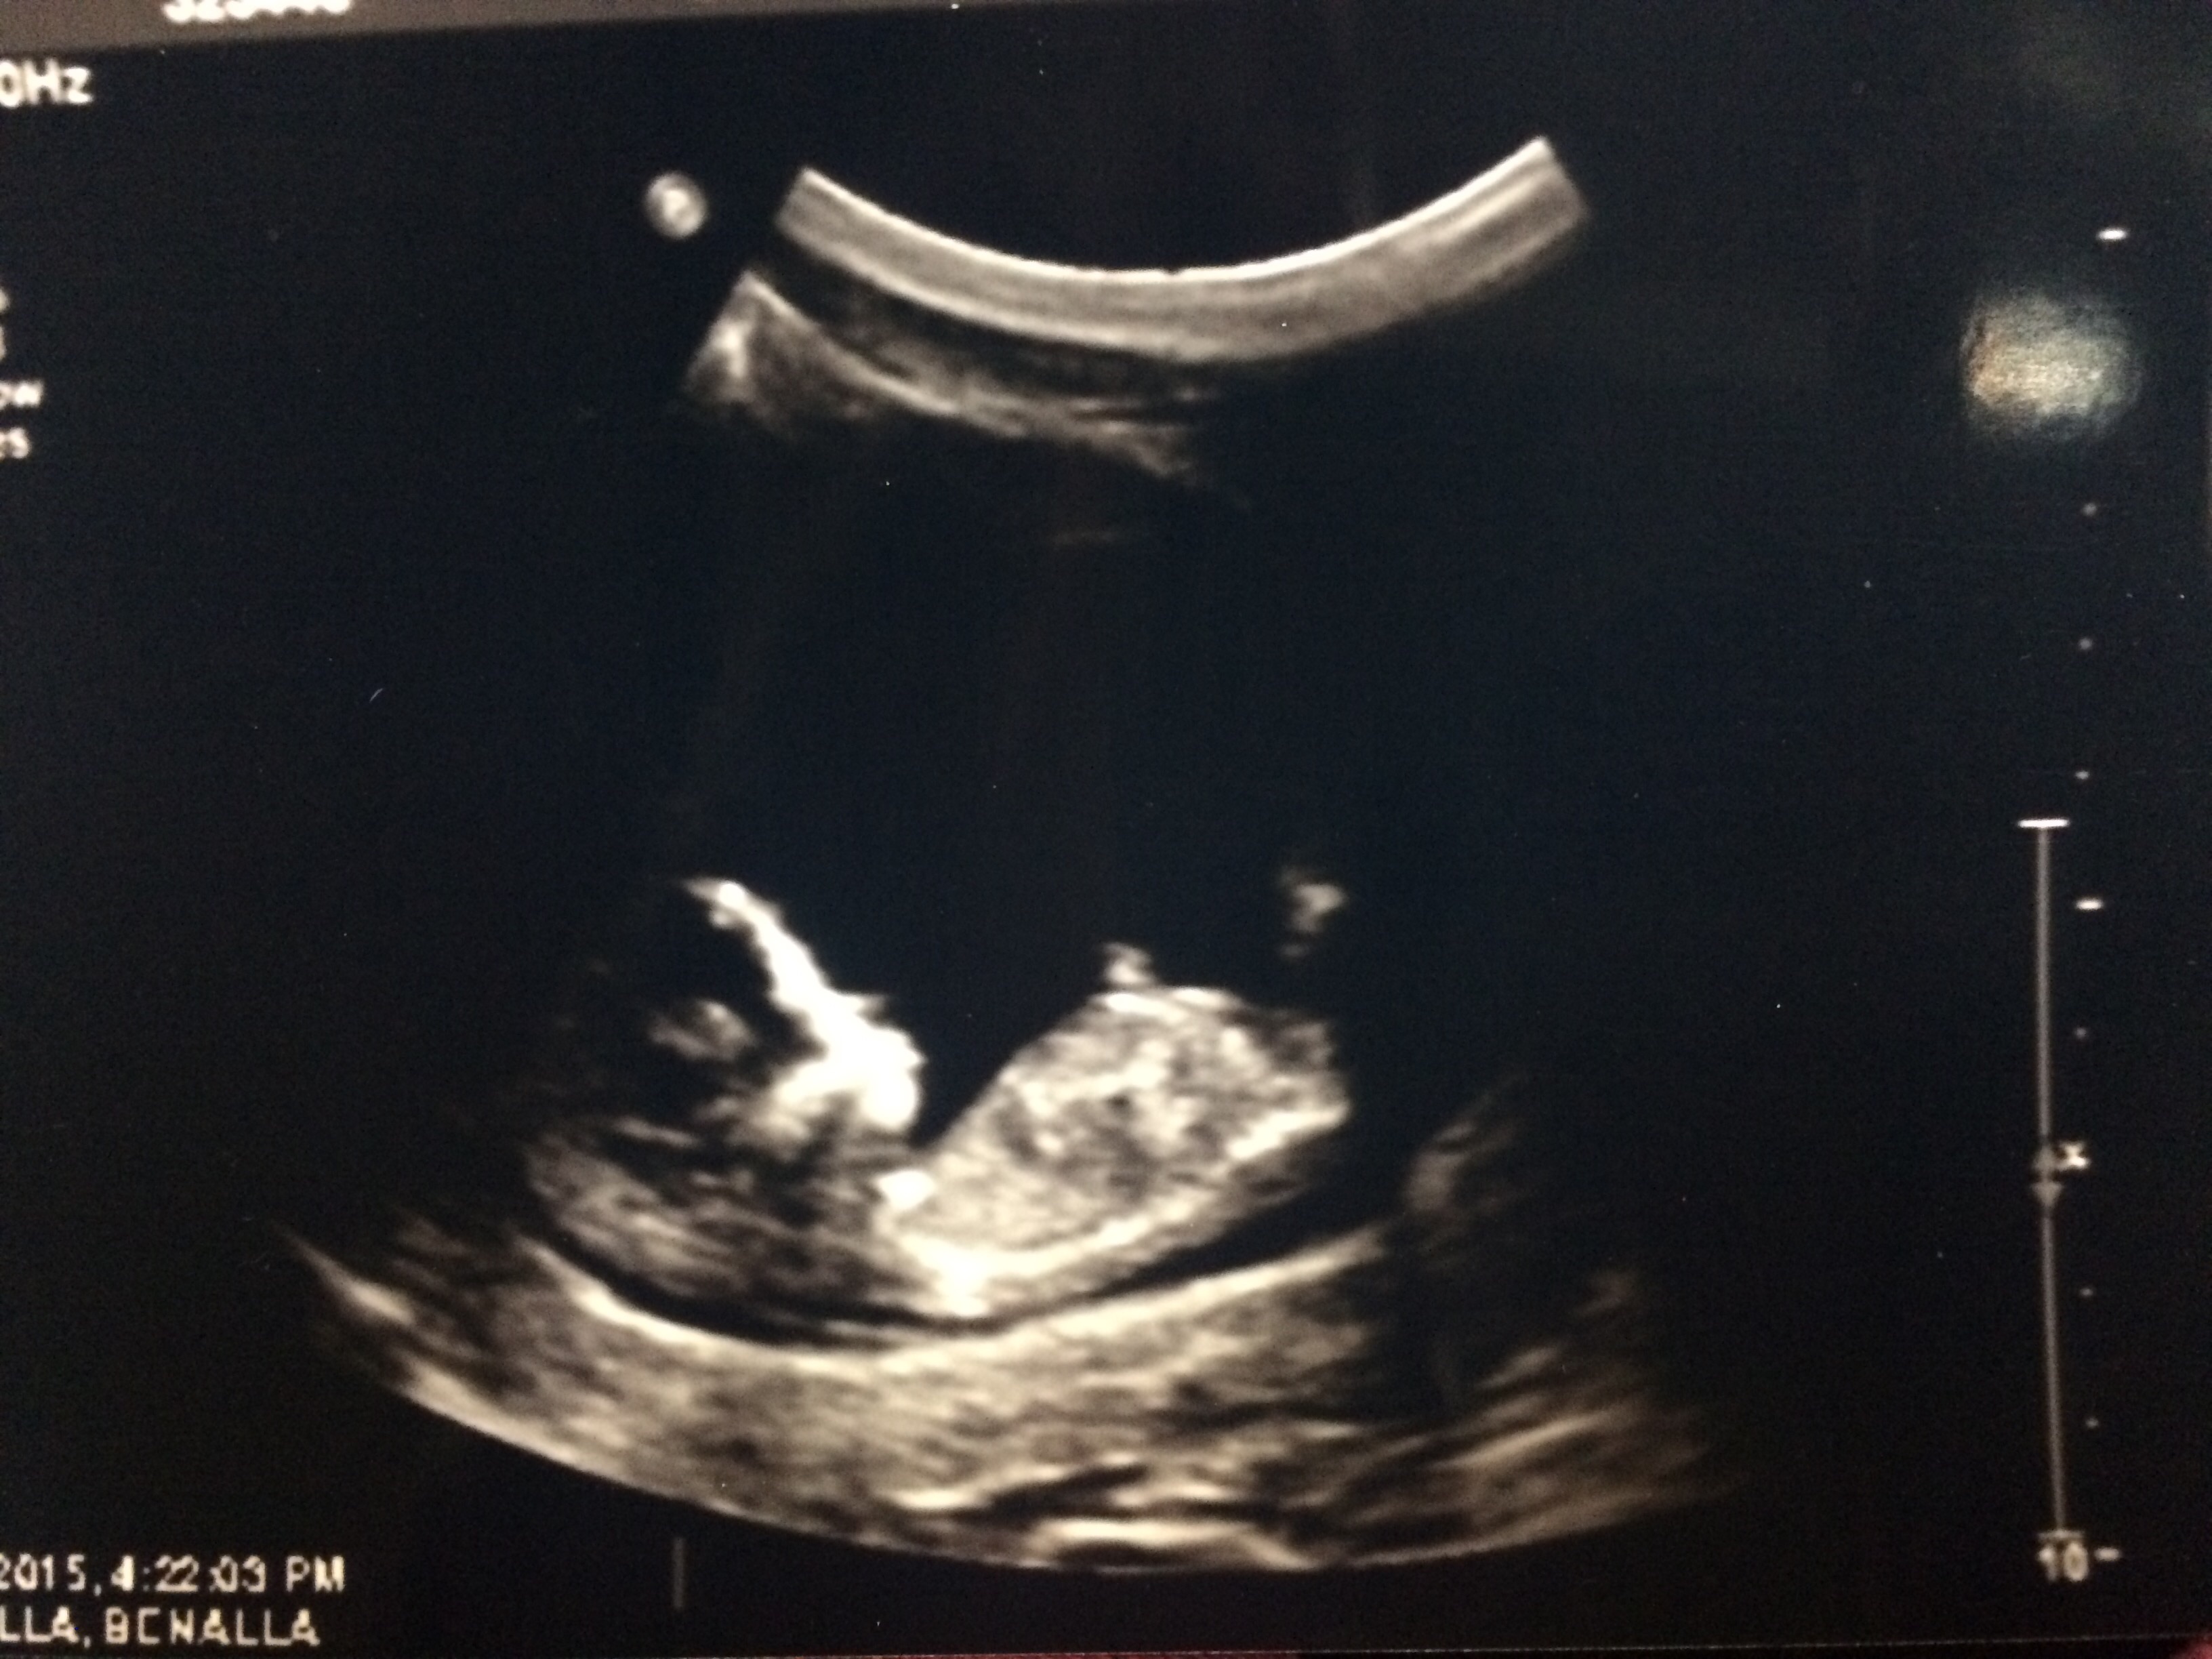

Our little one at 13 weeks 1 day! I didn't know you could have Braxton Hicks contractions this early - but apparently I was having one and it left baby a little squished and made it hard to get a good pic. Tech tried her best though! Loved seeing baby actually looking like a baby (instead of just a peanut) these days